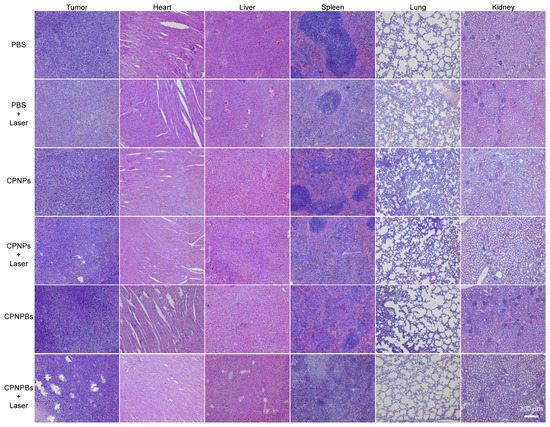

3.5. In Vivo Tumor Eradication and Biosafety of CPNPBs